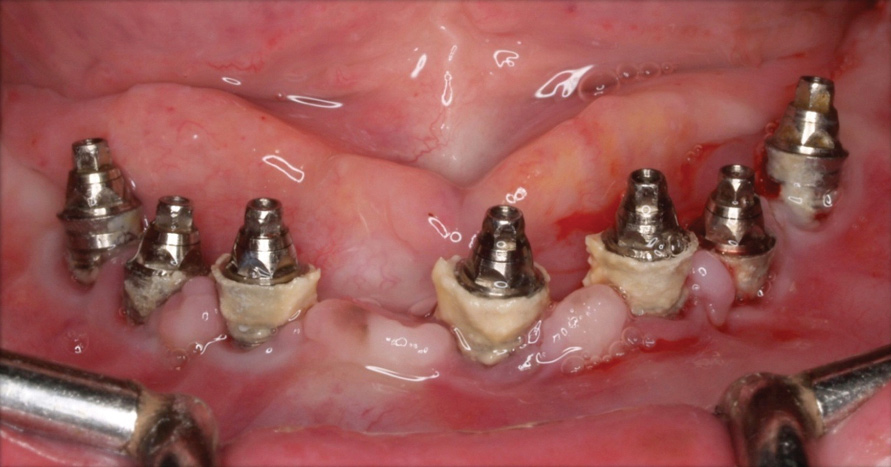

An important aspect of both professionally and patient-administered plaque removal is the cleanliness of the implant-supported restoration. A cohort study on 23 patients demonstrated that 74% of implants had no accessibility to proper oral hygiene and 48% of implants presenting with peri-implantitis were those that were not cleansable.17 The non-fitting or non-cleansable overhanging prostheses, therefore, should be considered iatrogenic factors that contribute to the development of peri-implantitis. Similarly, incorrectly positioned implants or foreign bodies such as impression material or excess luting cement can contribute to increased biofilm accumulation and hence favor the development of peri-implant diseases.10 Correction or elimination of these factors (eg, prosthesis removal and adjustment/replacement, if necessary) should be a principal component of the treatment of peri-implant mucositis (Figure 9 through Figure 11).

Fig 9. Treatment of peri-implant mucositis: plaque accumulation and mucosal inflammation.

Figure 9

Fig 10. Traumatic impingement of the pontic on the peri-implant mucosa.

Figure 10

Fig 11. After thorough mechanical debridement and modification of the prosthesis to allow cleansing.

Figure 11

Fig 12. Treatment of peri-implantitis: peri-implant mucosal inflammation associated with plaque and calculus accumulation.

Figure 12

Fig 14. After removing the prosthesis, presence of peri-implant plaque and calculus.

Figure 14

Fig 15. Access flaps to allow mechanical debridement of implant surfaces.

Figure 15